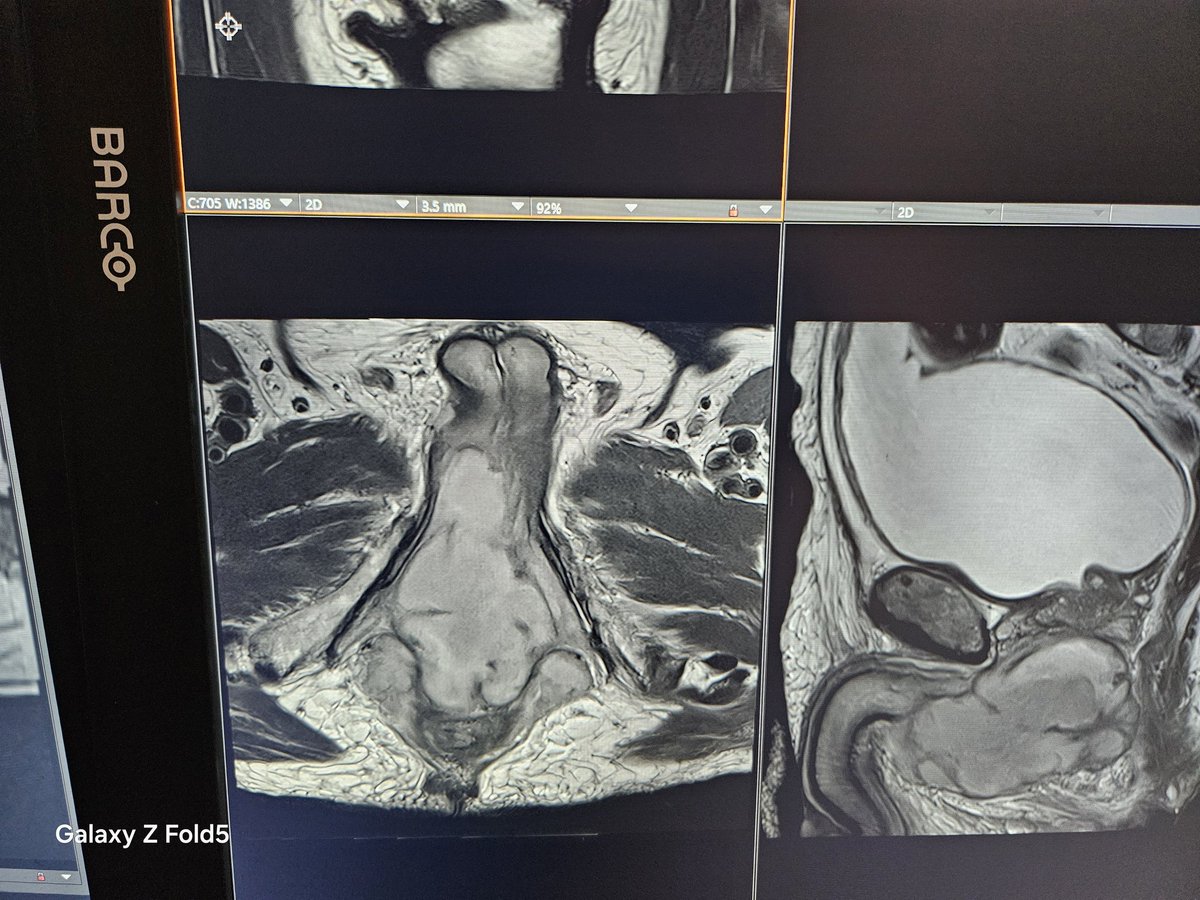

Your presentation at the prostate MRI hands-on course at SAR2026 was also greatly appreciated!